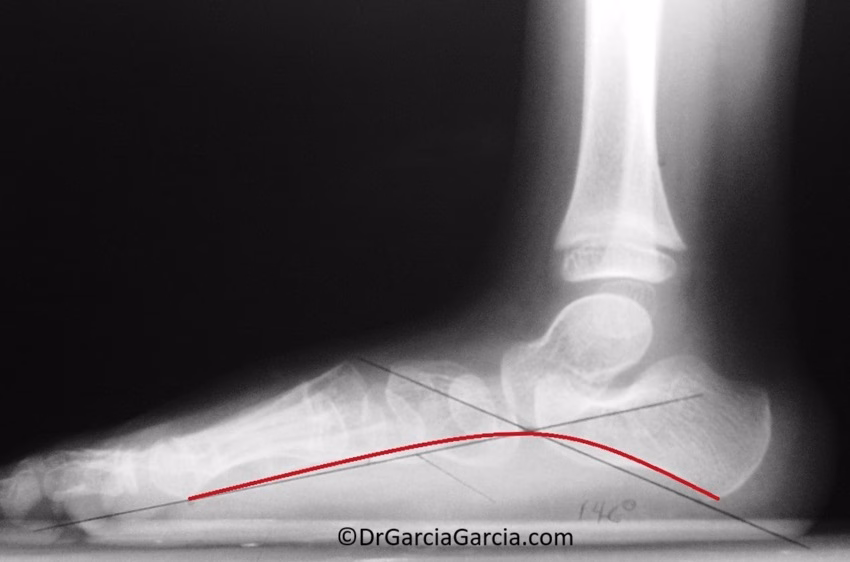

Figura 4. Bóveda plantar ósea en una radiografía lateral. a) En un pie normal. b) En un pie plano.